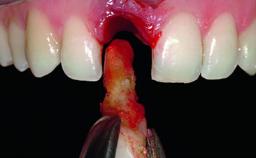

A 49-year-old female patient was referred for implant therapy to replace the upper right central incisor (tooth 11). The tooth had been assessed by an endodontist who diagnosed a vertical fracture of the root. The tooth had a hopeless prognosis and needed to be extracted. The patient was healthy and was not taking any medications. She was allergic to penicillin. The patient had high esthetic demands but her expectations were realistic. The extraoral examination revealed no facial asymmetries. The right temporomandibular joint demonstrated an opening click but was otherwise asymptomatic. The lip line was high with a significant gingival display.

Bone Augmentation Simultaneous|Vertical

Augmentation Materials Autogenous chips|Xenogenous|Membrane